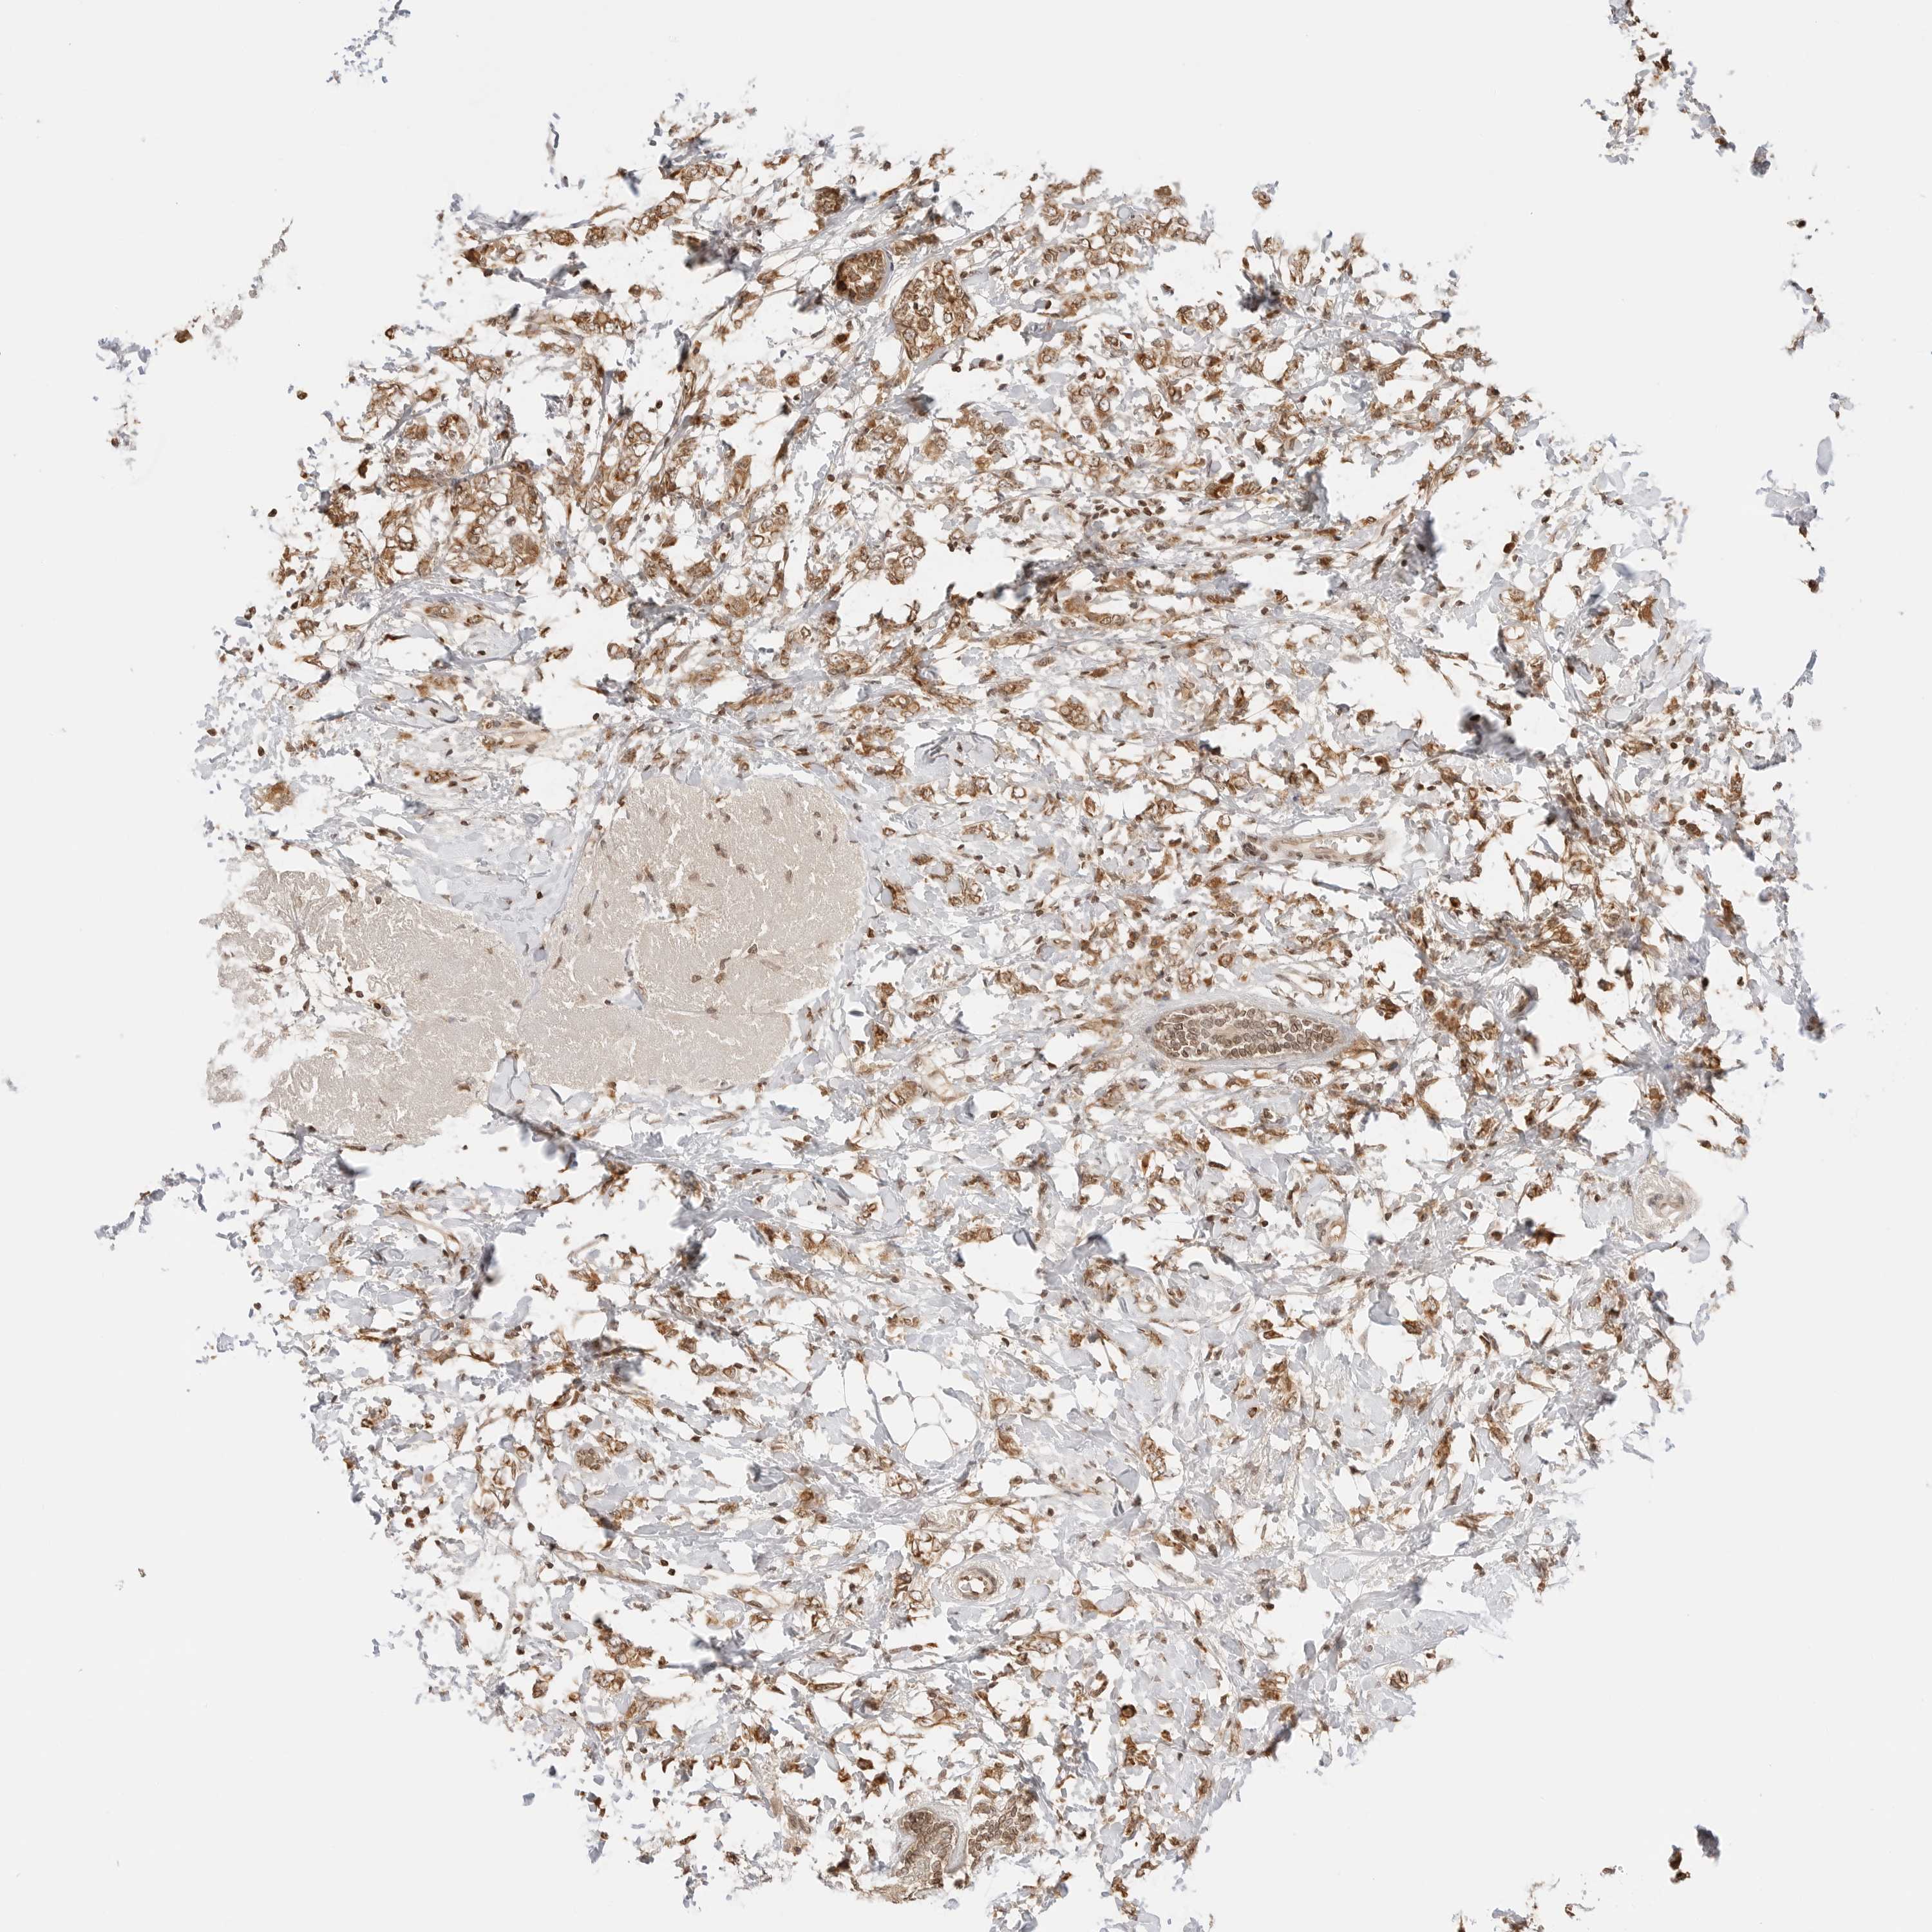

CANCER BREAST CANCER Show tissue menu

BRCA TCGA BRCA VALIDATION PROTEIN EXPRESSION